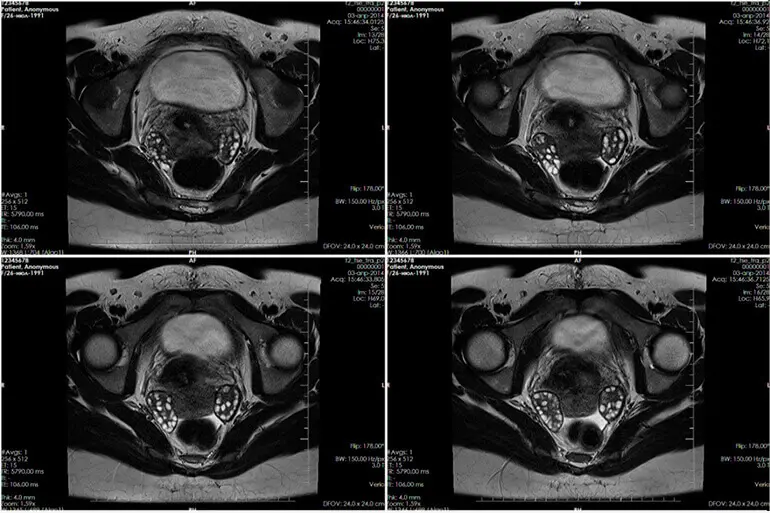

Розшифровка результатів

При виконанні розшифрування знімків МРТ лікар оцінює та описує всі видимі структури.

Особливу увагу приділяють стану:

- нервових закінчень, розташованих у тазовій області та куприка;

- лонних кісток, крижів, тазостегнових суглобів;

- передньої черевної стінки та її товщини;

- тазових органів;

- лімфовузлів;

- судин;

- м’язів та зв’язок.

Крім того, уточнюють наявність злоякісних та доброякісних утворень. Якщо вони є, вказують їх розмір, точне розташування, особливості структури, ступінь проникнення в тканини органу, характер кровопостачання та ін. Якщо каміння чи пісок є, описують їх розміри та локалізацію.

Крім того, при розшифровці лікар визначає наявність вільної рідини в порожнині малого тазу та відповідність її обсягу нормі.